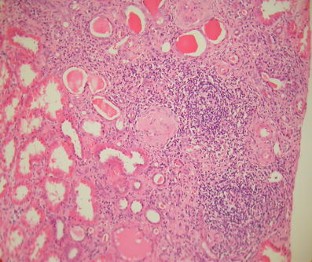

Fig. 1

We describe two adolescents who presented with end-stage renal failure and clinical features suggestive of Sjögren’s syndrome (SS). They both demonstrated severe, chronic, tubulointerstitial inflammation on renal biopsy, high-titre antinuclear antibodies, high immunoglobulin A and G concentrations, positive anti-SSA and anti-SSB antibodies, and negative anti-double-stranded DNA antibodies. One had subjective and objective evidence of the sicca complex (dry eyes and/or dry mouth) and fulfilled the commonly accepted SS consensus criteria. The other showed no evidence of the sicca complex but fulfilled modified criteria for juvenile SS. SS may be underrecognised as a cause of end-stage renal failure in childhood.